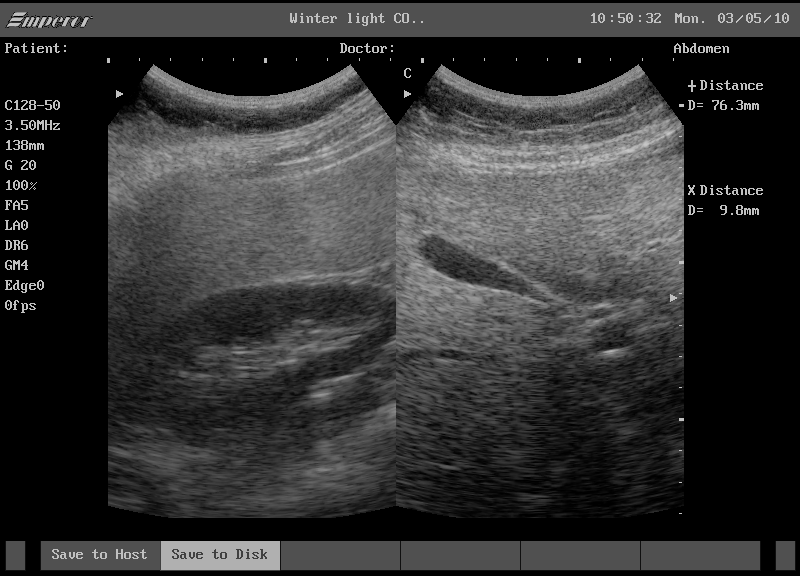

복부 초음파(Abdominal Ultrasound)는 인체에 해가 없는 음파, 즉 초음파를 사용하여 간, 담낭, 신장, 비장, 췌장 등 복부 장기의 형태와 상태를 확인하는 검사입니다. 흔히 “초음파와 방사선 관계”를 궁금해하시는 분들이 있는데, 기본적으로 초음파는 방사선(X선)을 사용하지 않습니다. 따라서 임신부도 안심하고 검사를 받을 수 있으며, 여러 번 반복해도 방사선 피폭에 대한 걱정이 없다는 것이 큰 장점입니다.

결과 영상을 보면 까만색, 회색, 흰색 영역이 모자이크처럼 보이는데, 이를 통해 장기의 경계, 혹이나 낭종 여부 등을 판별할 수 있습니다. 예를 들어 “신장에 혹과 낭종의 차이”를 진단할 수 있는 것도 초음파로 비교적 쉽게 확인이 가능합니다. 최근에는 해상도가 높은 장비들이 많이 보급되어, 수 밀리미터 단위의 이상도 찾아낼 수 있어 더욱 믿음이 가는 검사죠.